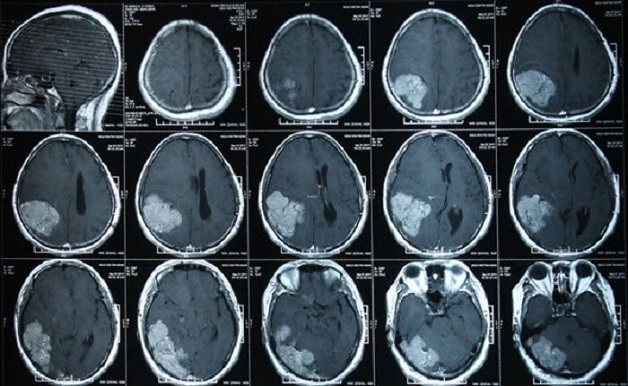

Chụp cắt lớp hay còn gọi là chụp CT, là kỹ thuật chẩn đoán hình ảnh sử dụng hàng loạt tia X quang để quét lên các vị trí cần kiểm tra từ nhiều góc khác nhau theo các lát cắt ngang. Sau đó, kết quả chụp sẽ được thu lại trên máy vi tính dưới dạng hình ảnh 2D hoặc 3D.

Kỹ thuật này có thể hình ảnh hoá hầu hết các bộ phận trên cơ thể như đầu, vai, xương sống, tim, bụng, đầu gối, ngực,… và kết quả thường rõ nét hơn so với phương pháp chụp x quang.